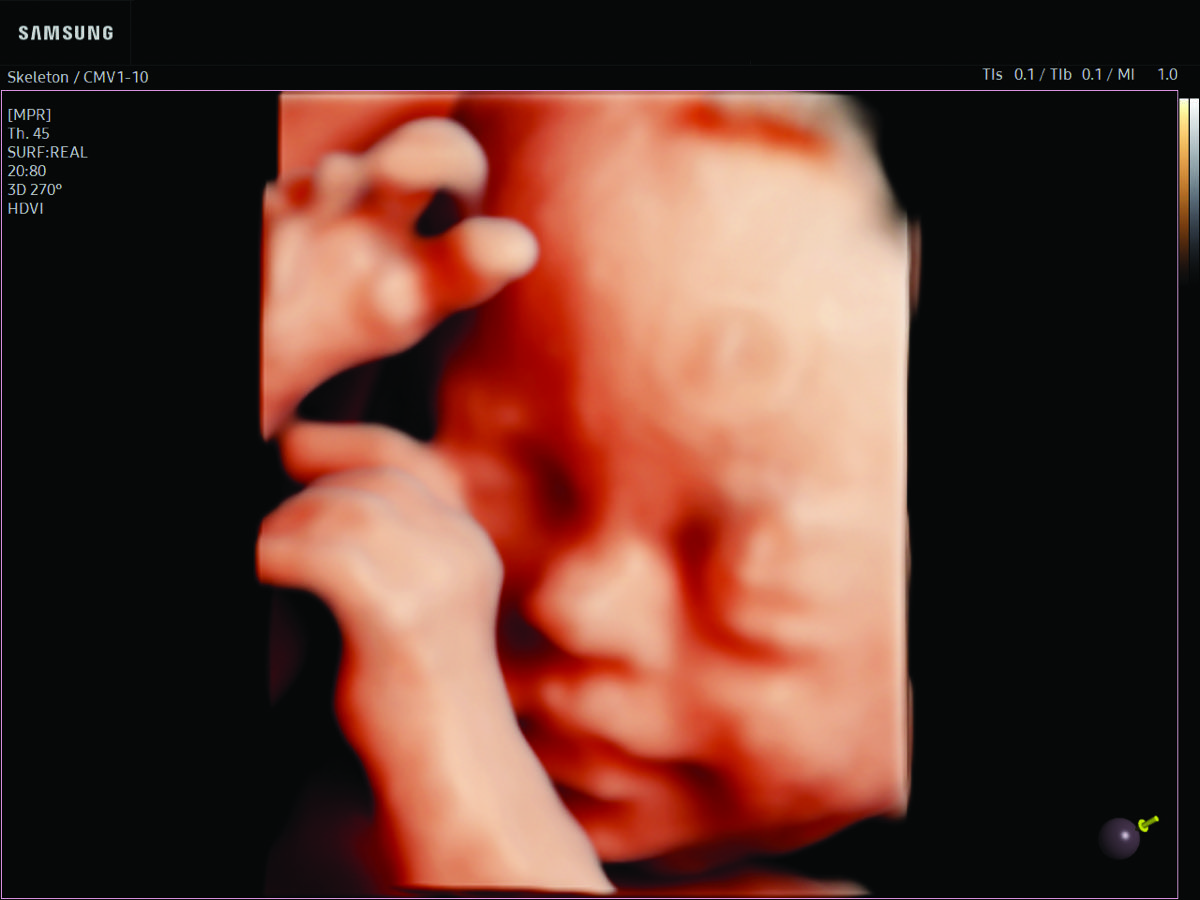

Comprehensive, advanced and expert MFM care for high-risk pregnancies

- Fetal anomalies